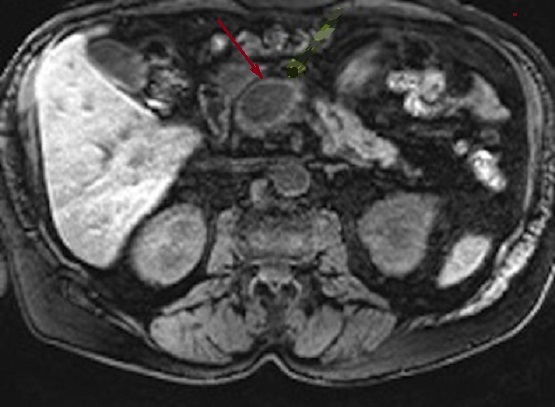

Image de pseudokyste d'une

pancreatite chronique tardive ( fleche rouge ) . Sa

contenue interieure est souvent 20UI et changement

de densite dans cas infection ou hemorragique |

Aspect de dilatation

hyperintense du canal pancreatique principale avec

image du calcul a hypointense au tete du pancreas .

Pancreas est atrophique hyposignal . Image

radiologique IRM pondere T2 en coupe axiale |